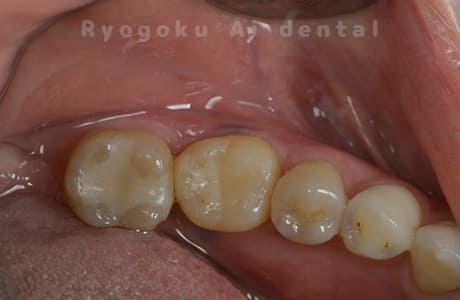

Case12

-

- 原因

- 歯牙破折

- 治療内容

- 自家歯牙移植

- 治療費用

- 220,000円

右上の違和感が取れず、ご来院された患者様です。歯が割れており、抜歯を行い、反対側の親知らずを移植しました。

<リスク・副作用>

治療後、痛みや違和感、出血、腫れなどが出る事があります。喫煙者、糖尿病などの方の場合、歯が生着しない場合があります。